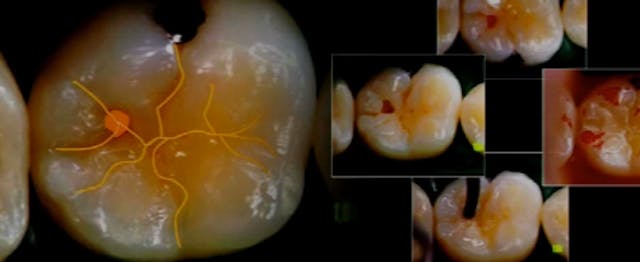

Composite Resins in Contemporary Practice